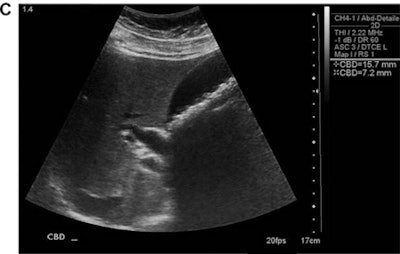

The conventional ultrasound studies were performed by sonographers certified by the American Registry for Diagnostic Medical Sonographers (ARDMS) on an HD-5000 (Philips Healthcare), IU-22 (Philips), E-8 (GE Healthcare), or Antares (Siemens Healthineers) scanner. The study's senior author, Dr. Robert Harris, read the exams immediately after they were performed; these interpretations served as the reference diagnostic standard and were confirmed or modified one year after patient enrollment based on further clinical evaluation and follow-up, laboratory/pathologic data, and additional imaging studies. Harris, who has 23 years of general ultrasound experience and 10 years of compact ultrasound experience, then performed all point-of-care ultrasound studies using a SonoSite 180 Plus scanner (Fujifilm SonoSite). The point-of-care exams were targeted, focused exams that took two to three minutes to perform.

High image-quality scores (4 or 5) were given to just 27% of point-of-care ultrasound studies, and reader accuracy was lower in point-of-care ultrasound studies with an image quality rating of 3 or less.